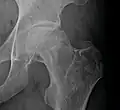

X-ray images of avascular necrosis in the early stages usually appear normal. In later stages it appears relatively more radio-opaque due to the nearby living bone becoming resorbed secondary to reactive hyperemia.[2] The necrotic bone itself does not show increased radiographic opacity, as dead bone cannot undergo bone resorption which is carried out by living osteoclasts.[2] Late radiographic signs also include a radiolucency area following the collapse of subchondral bone (crescent sign) and ringed regions of radiodensity resulting from saponification and calcification of marrow fat following medullary infarcts.